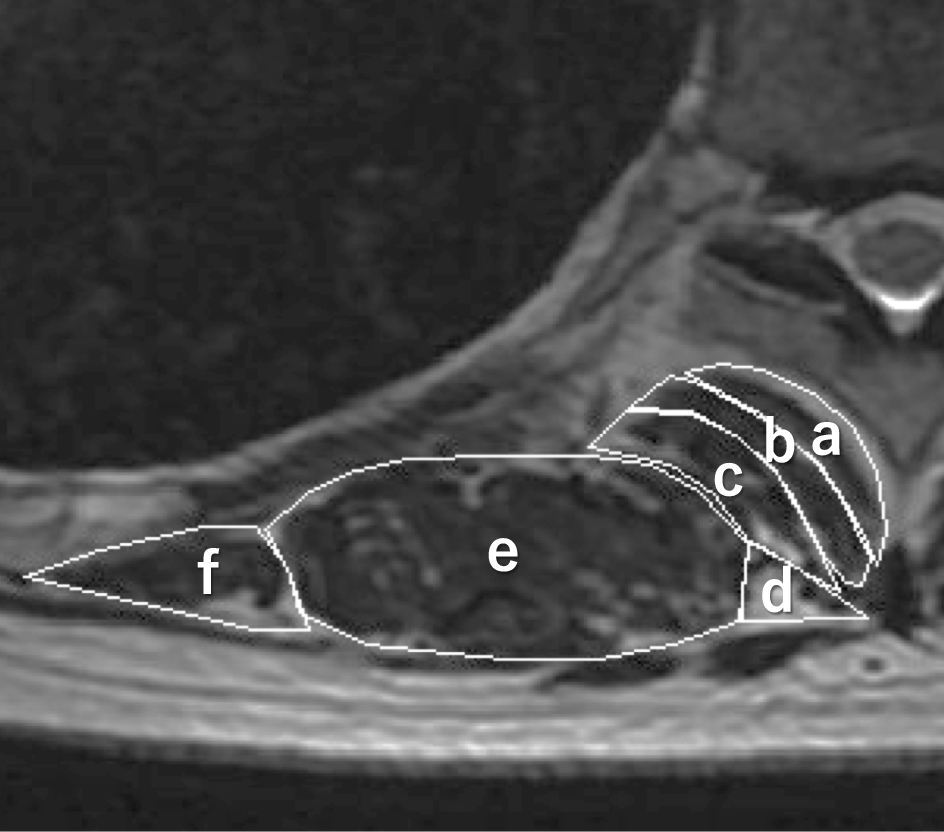

Figure 2

Posterior extensor muscles visualized on an axial T2-weighted image. The cross-sectional area of the transversospinalis muscles (a, rotatores; b, multifidus; c, semispinalis), erector spinae muscles (d, spinalis; e, longissimus; f, iliocostalis) were measured by using the calibrated scale on the MR images.